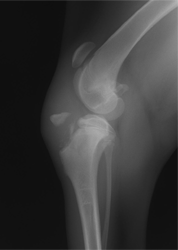

■ 症例3

中型犬の大腿骨骨折

DCPプレートによる固定